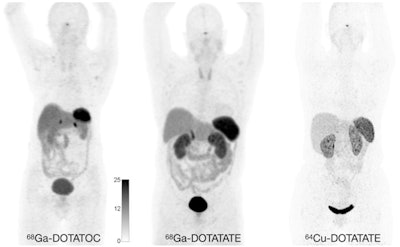

Specifically, SSTR PET imaging with gallium-68 (Ga-68) DOTATATE, Ga-68 DOTATOC, and copper-64 (Cu-64) DOTATATE can improve the sensitivity of lesion detection, lower radiation dose, and provide shorter and more convenient study durations. The new guideline focuses on these PET radiotracers.

Normal biodistribution in patients of the radiotracers Ga-68 DOTATOC, Ga-68 DOTATATE, and Cu-64 DOTATATE. Image courtesy of the Journal of Nuclear Medicine.The guideline addresses common clinical indications, qualifications and responsibilities of personnel, specifications of the examination, documentation and reporting, and dosimetry. It also presents standardized quality control procedures for SSTR PET, as adequate precision, accuracy, repeatability, and reproducibility are essential for the clinical management of patients and the use of SSTR PET within multicenter trials, the authors noted.